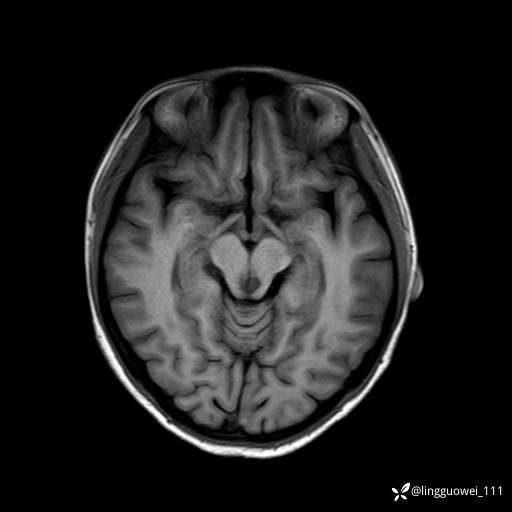

T1

img